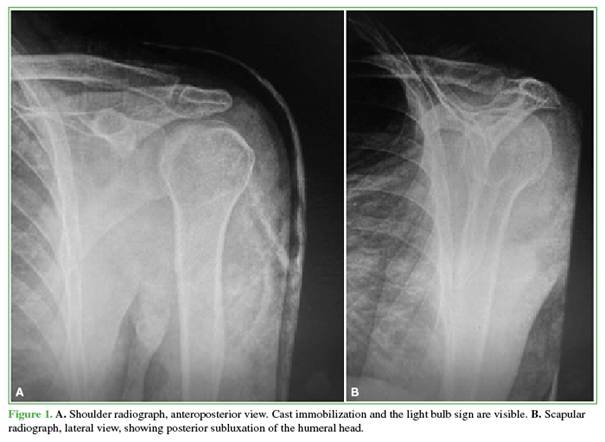

Inclusion criteria were: acute dislocations reduced in the Emergency Department; treatment of instability within the second or third week after the episode; reverse Bankart lesion; and a reverse Hill–Sachs lesion involving up to 30% of the humeral head (Figures 1 and 2).

Operative time ranged from 80 to 150 minutes (mean, 100). There were no redislocations, infections, or signs of instability in any of the 3 patients (Figure 7).